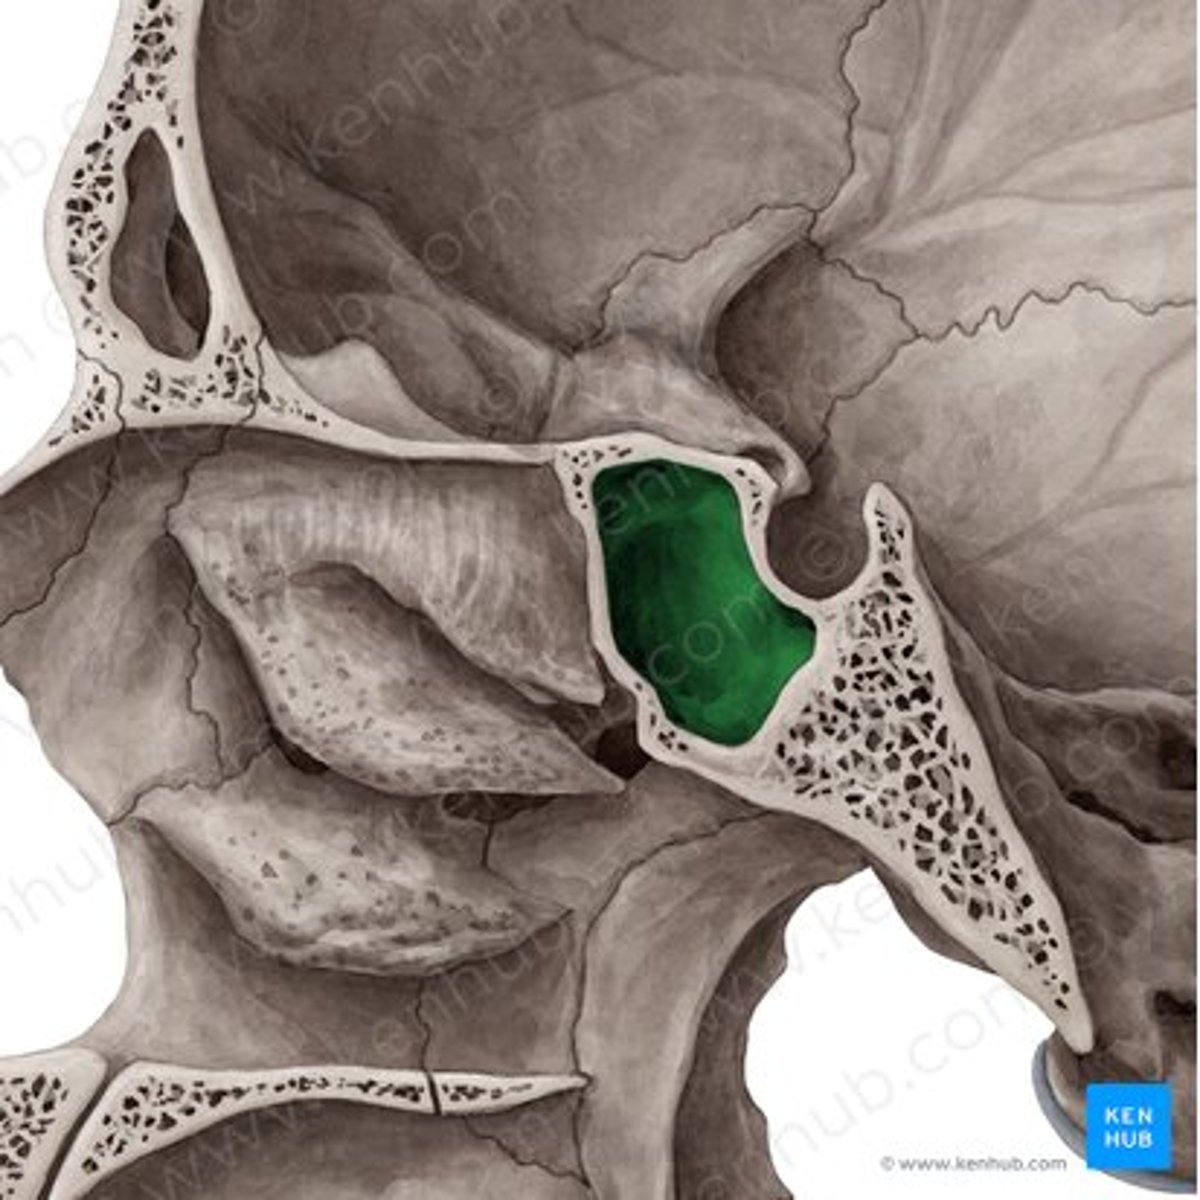

sigmoid sinus